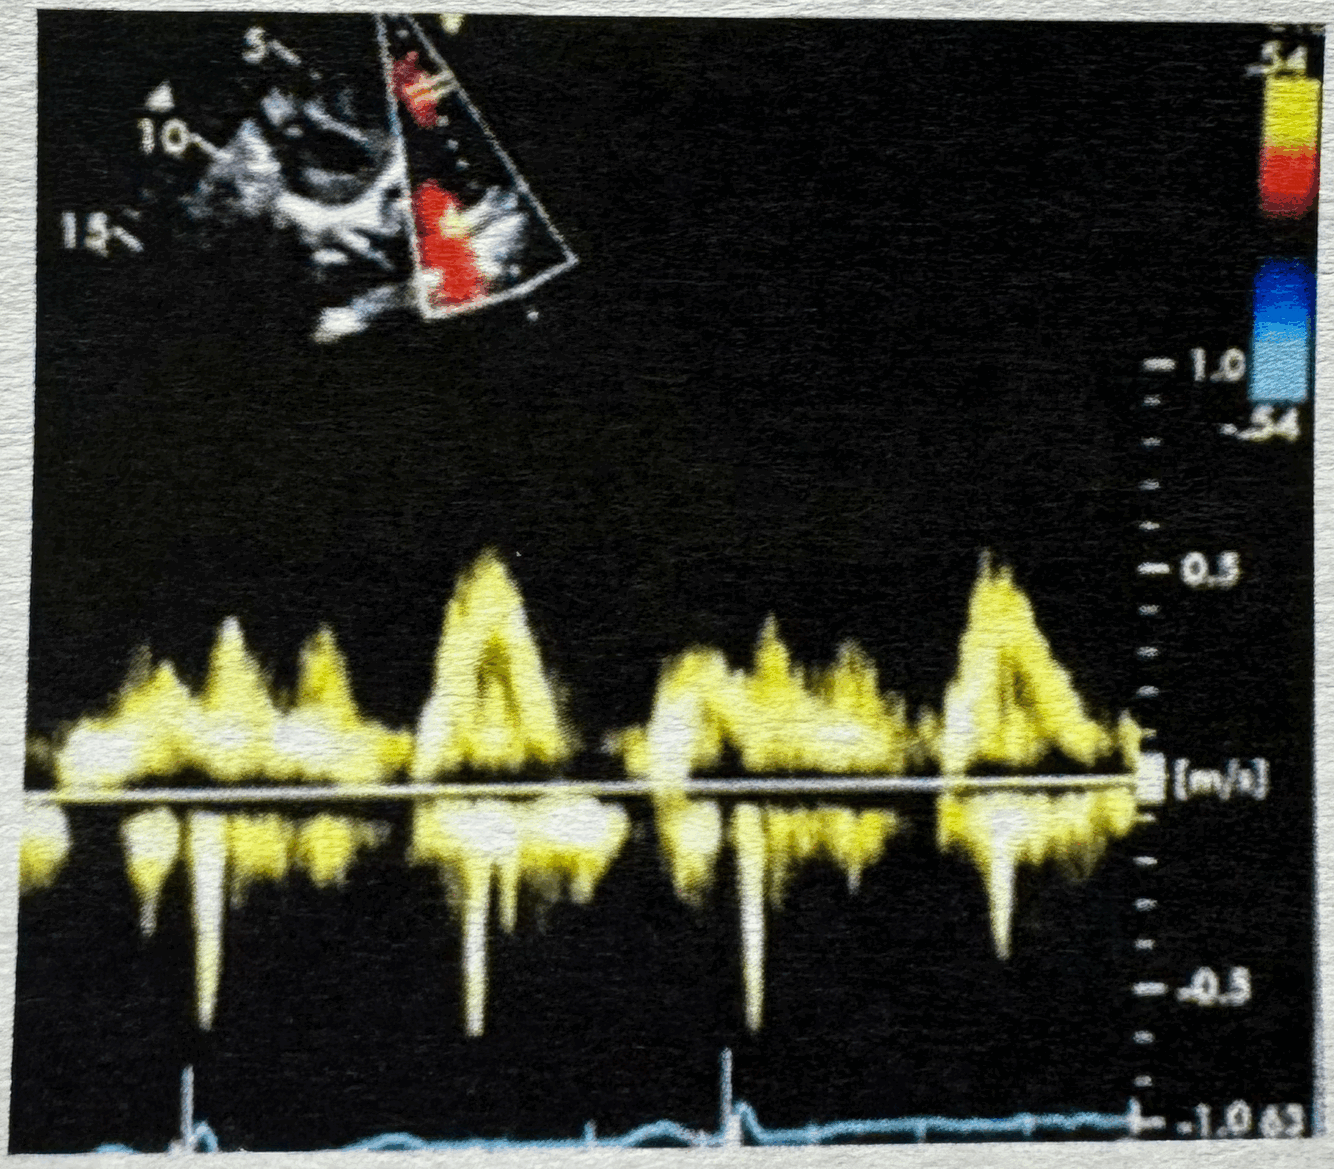

What waveform is this and is it PW or CW?

22